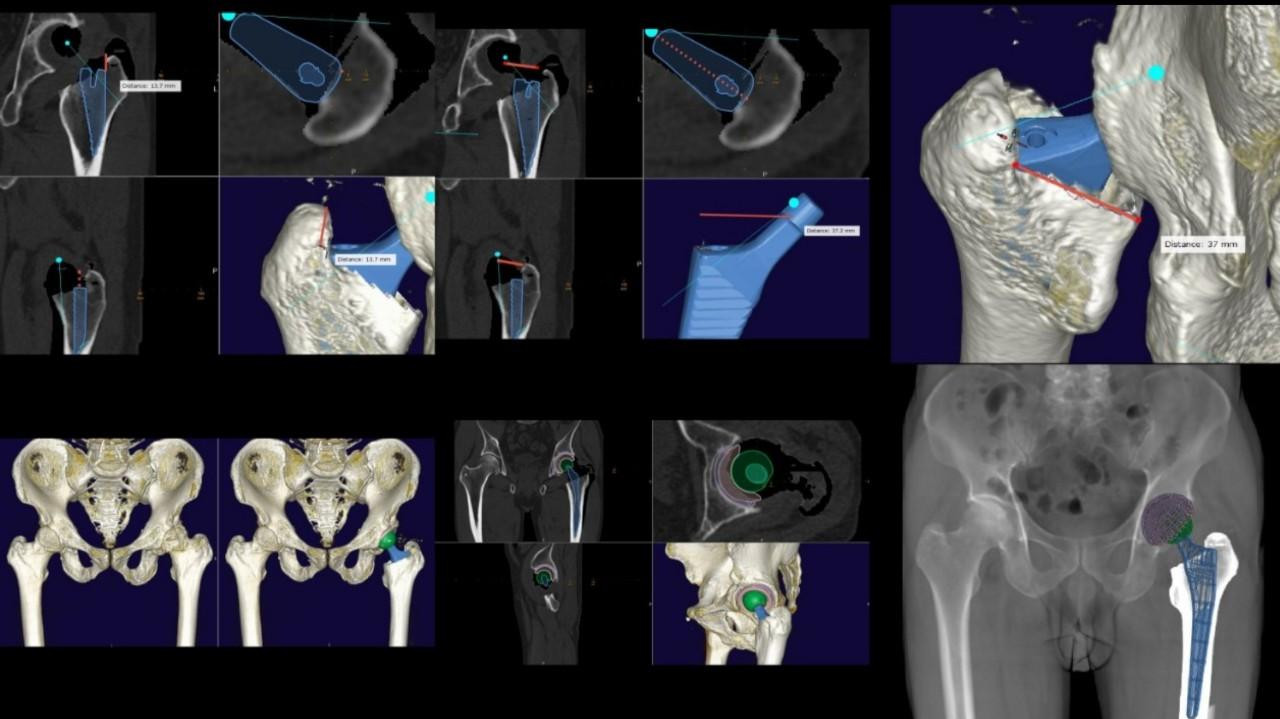

| Hình ảnh kế hoạch phẫu thuật khớp háng được mô phỏng trên máy tính trước mổ |

Sau khi đã lựa chọn được loại khớp nhân tạo thiết kế theo đặc điểm cá thể hóa, các bác sĩ sẽ sử dụng các phần mềm chuyên dụng để lập kế hoạch chi tiết cuộc mổ. Quá trình này giúp xác định chính xác vị trí cần đặt các cấu phần khớp nhân tạo nhằm tối ưu hóa biên độ vận động của khớp sau mổ, tránh mọi rủi ro cứng khớp hay đi lại tập tễnh. Đồng thời sẽ tiên lượng được một số rủi ro có thể xảy ra xuyên suốt quá trình phẫu thuật. Thậm chí bệnh nhân và người nhà còn có thể tham gia với bác sĩ để có thể hiểu rõ một cách trực quan nhất những điều gì sẽ có thể xảy ra với cuộc phẫu thuật của bản thân.